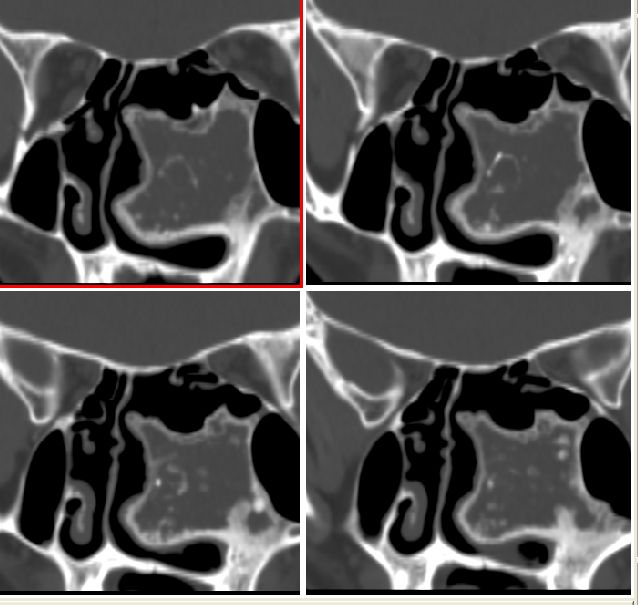

男性,20岁,面部包块8年余,进行性增大

左侧鼻腔内囊性膨胀性骨质破坏,内示多发点环状钙化,周边骨质硬化.局部与上颌相连部骨质呈毛玻璃样改变.

左侧鼻腔内囊性膨胀性骨质破坏,内示多发点环状钙化,周边骨质硬化.

良性病变。骨化性纤维瘤首先考虑。

左侧上颌骨骨化性纤维瘤.

左侧上颌骨化牙骨质纤维瘤